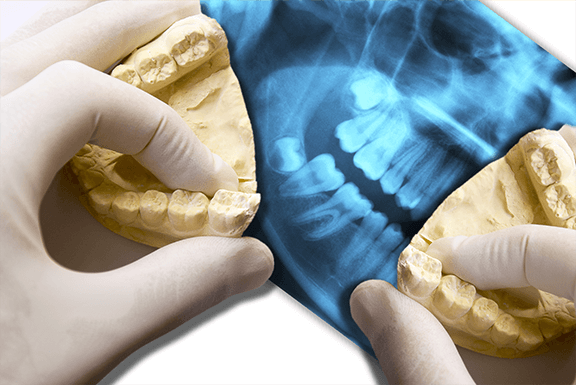

Wisdom tooth removal is a fairly common procedure. If the dentist

thinks that you need to have your wisdom tooth removed, he will

first have to confirm it through an X-ray of your mouth. This gives

him a clearer view of how your teeth are positioned.